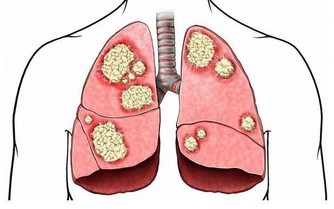

牙周病與維生素和礦物質的缺乏相關。鈣、磷、鋅、葉酸、鐵、ω-3脂肪酸、維生素B、維生素A、C和D都與口腔的健康息息相關。防止蛀牙的最好辦法就是養成攝取瘦肉蛋白質與新鮮蔬菜的飲食習慣。